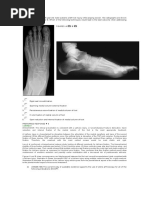

Foot & Ankle

MSK SERVICES PATHWAY - FOOT & ANKLE PATHOLOGY